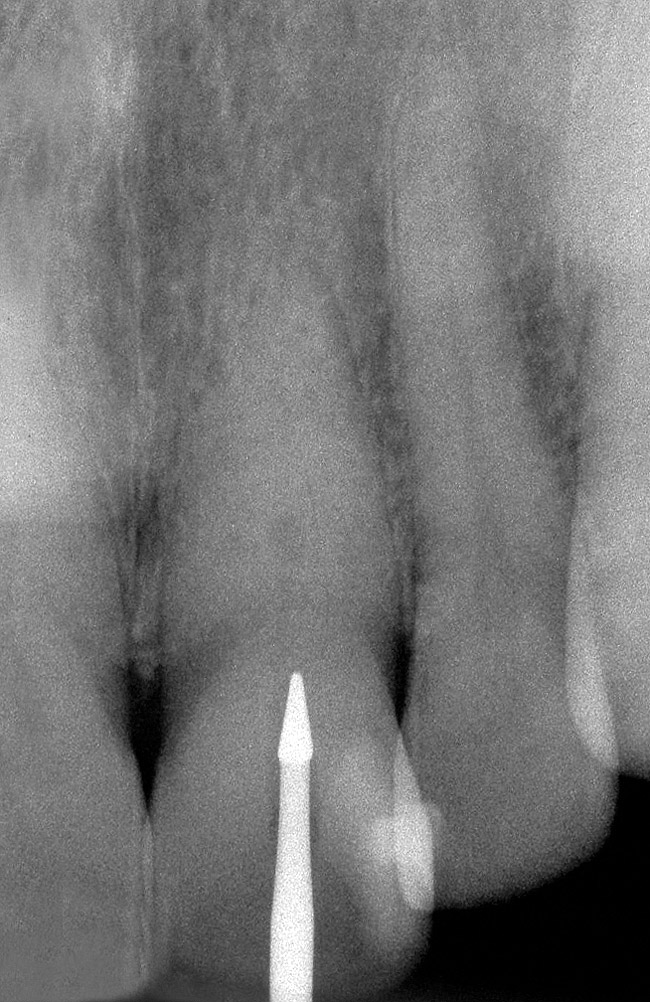

The feature case of this article, highlighted in Figure 13 through Figure 24, demonstrates a comprehensive shift in many aspects of endodontic access. The calcified central incisor ( Figure 13) of a 42-year-old woman was treatment planned for elective endodontics to facilitate internal bleaching for esthetic reasons. The preoperative radiograph demonstrated almost complete obliteration of the pulp, except for a small pouch in the center of the root. Referring these challenging cases to a microscopeequipped endodontist should always be considered. However, many well-trained general dentists attempt these difficult cases, and most dentists routinely deal with partially calcified cases. Still, the concepts forwarded in this case can be employed as indicated in every endodontic access treatment.

The resultant cavosurface outline is quite long and fairly narrow for the calcified tooth, and creates better potential for accuracy ( Figure 18 and Figure 19). A final view of the access in Figure 20 shows the orientation of the palatal–incisal notch and the dentinal map, which is encountered as early as possible. The radiographic sequence ( Figure 21, Figure 22, Figure 23 and Figure 24) teaches a new concept in accessing calcified canals, that of radiographs taken using the pointing quality of a conical bur to assess direction and position of the access cavity. Corrective steps can then be taken to avoid gouging or perforation. In the past, only endodontic files have been used as metallic (radiopaque) radiographic markers. The snug fit of a conical bur as opposed to the loose fit of a round bur facilitates the use of the bur in taking "bur instrument films."